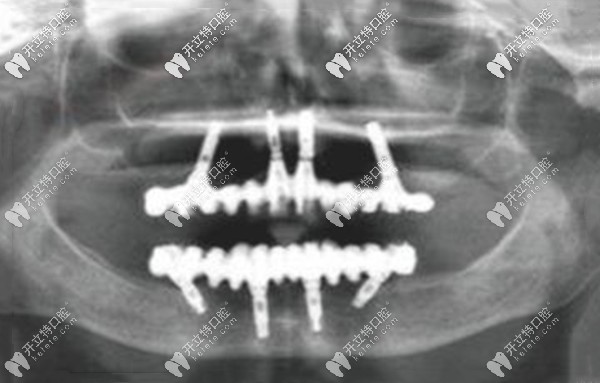

從上圖可以看出,高先生的滿口只剩下兩顆“搖搖欲墜”的牙齒,牙槽骨明顯能看出來吸收、萎縮,高度明顯降低;這就是之前假牙脫落的真正原因。

爾睦口腔肖步挺醫(yī)生對高先生的口內拍CT片檢查后,評估了牙槽骨的厚度、密度、高度、上下頜的咬合關系,為其設計了目前比較先進的All-on-4全口咬合重建的種植牙方案。

allon4即刻負重種牙,也就是上、下頜各植入4顆植體(兩顆純直植入、兩顆傾斜植入),再搭配覆蓋義齒,就能發(fā)揮全口的咬合力,而且是當天種、當天戴臨時牙冠、當天就能吃東西。

深圳沙井爾睦口腔肖步挺院長給高先生做的allon4全口種植牙,全程用的是數(shù)字化種植方式,傷口比較小、安全性也高,比較適合老年人的半口及全口無牙的情況~~~